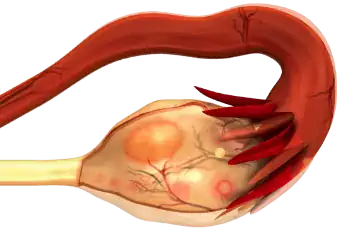

ציסטה בשחלה

ציסטה בשחלה - המדריך עם כל המידע הרפואי והמעודכן ציסטה היא מעין שק מלא בנוזל או חומר נוזלי למחצה (מוגלה למשל), שנוטה להצטבר במיקומים שונים בגוף אבל רק לעיתים נדירות מתפתח לכדי מצב רפואי חריף. מוערך כי אצל מעל 95% מהנשים מתפתחת